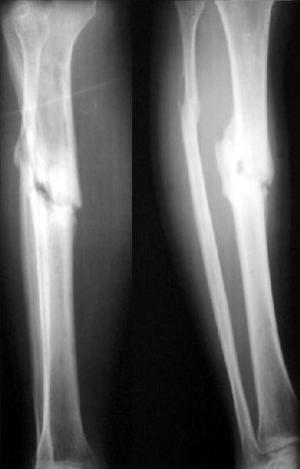

Псевдоартроз плечевой и других костей можно без труда выявить при рентгенологическом исследовании.

Различают два вида ложных суставов — гипертрофический и атрофический. В первом случае при нормальном кровоснабжении начинает избыточно разрастаться костная ткань, однако это приводит только к развитию большого расстояния между отломками.

Второй вид формируется при отсутствии или недостаточности кровоснабжения в месте травмы. Части одной кости соединены между собой соединительной тканью, но к сожалению, она не способна удерживать место перелома в хорошо зафиксированном состоянии.